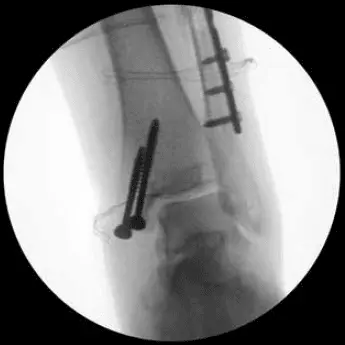

Na rehabilitację trafiła kobieta, lat 25, która w wyniku nieprawidłowego lądowania przy drugim kursie na AFF doznała wieloodłamowego złamania kości strzałkowej lewej, kostki przyśrodkowej i krawędzi tylnej piszczeli. Kończynę unieruchomiono w ortezie typu walker. Wykonano zabieg zespolenia złamania kostki bocznej płytą Medal – mocowana dwoma śrubami korowymi i czterema śrubami blokowanymi. Zespolenie kostki przyśrodkowej dwoma śrubami kostkowymi.